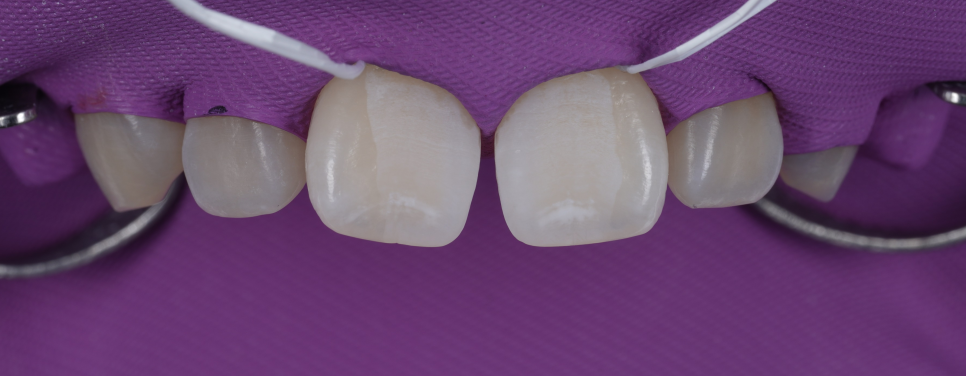

치아 표면을 깨끗하게 한 뒤, 러버댐을 장착하고 치료를 시작했어요.

촬영 : 251030

접착이 잘될 수 있도록 표면처리 과정도 꼼꼼하게 진행했습니다.